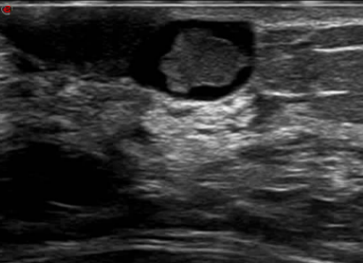

乳腺超声

对乳腺导管的解剖结构及局部血流动力学特征进行评估。